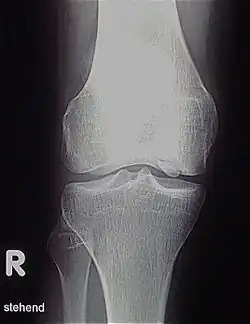

Die Erkrankung kann zufällig auf einem Röntgenbild entdeckt werden, das nach einem Unfall von der Knieregion, vom Sprunggelenk oder vom Ellbogen angefertigt wird. Bei typischen Beschwerden von aktiven Kindern und Jugendlichen kann mit einem solchen einfachen Röntgenbild die eindeutige Diagnose schon gestellt werden, weil der veränderte Knochen unterhalb der Gelenkoberfläche an typischer Stelle in der Oberschenkelrolle am Knie identifiziert werden kann. Manchmal kann eine sogenannte Tunnelaufnahme mit gebeugtem Knie die Schädigungszone noch besser zeigen. Zur genaueren Analyse sollte eine Kernspintomographie (MRT) durchgeführt werden. An den dabei erzeugten Bildern lässt sich die Lage und Größe des Befundes, die Tiefenausdehnung und vor allem eine Beteiligung des darüberliegenden Knorpels genau ausmessen. Es sind damit auch Aussagen zur Stabilität des Befundes zu treffen. Daraus ergeben sich dann entscheidende Anhaltspunkte für therapeutische Konsequenzen. Für die Verlaufsbeurteilung der Erkrankung eignet sich am besten das MRT, aber ggf. auch wieder die einfache Röntgenuntersuchung. Aufgrund der extrem hohen Kosten für das MR in den USA werden die Verläufe dort bis heute weitgehend nur mit Röntgenbildern dokumentiert, was zu eigenen Empfehlungen zur Verlaufsbeurteilungen führt. Generell wären aber die MR-Untersuchungen das Verfahren der Wahl. Sie erlauben eine differenzierte Beurteilung der unterschiedlichen Kriterien für Ausheilung, Instabilität und drohende Dissektion. Untersuchungen mit Sonographie können zuverlässige, aber nur orientierende Befunde am Femurkondylus erheben. Es ist damit zum Beispiel ein schneller, kostengünstiger und sicherer Ausschluss des Befalls auch der Gegenseite möglich.